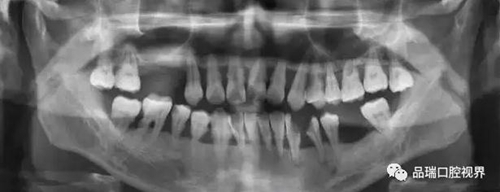

牙周炎是由于牙結(jié)石過多刺激所引起的。對(duì)于牙周炎的治療,可以通過洗牙去除牙結(jié)石從根本上預(yù)防牙周炎的發(fā)生。但事實(shí)上,當(dāng)大家說起“潔牙”時(shí),許多人的內(nèi)心確實(shí)是矛盾的。一方面,深深地明白一年1-2次的潔牙是口腔健康的必備作業(yè)。但另一方面,潔牙時(shí)產(chǎn)生的酸痛和不適感卻又讓人覺得不那么愉快。

刷牙出血、牙齦紅腫、疼痛,這種情況幾乎人人都有過。在疲勞、生活不規(guī)律,刷牙潦草時(shí)更容易出現(xiàn)。很多朋友以為牙齦出血是因?yàn)槿狈δ撤N維生素。其實(shí),雖然長(zhǎng)期嚴(yán)重缺乏維生素C確實(shí)會(huì)導(dǎo)致牙齦出血紅腫,但除非一連兩三個(gè)月都不吃蔬菜水果牛奶等含有維生素C的食物,否則,除了極少數(shù)人是由于血液病等全身疾病,絕大多數(shù)牙齦出血都是牙齦炎的表現(xiàn)。牙齦出血,原因多為牙齦炎或牙周炎。

牙周炎是一種漸進(jìn)性的疾病——就是說它并不會(huì)像普通感冒一樣,不管治不治療,只要不繼發(fā)感染,一周左右都會(huì)好。如果不對(duì)炎癥和口腔的刺激因素進(jìn)行控制,牙齦炎會(huì)進(jìn)一步發(fā)展為牙周炎,這就不再是僅限于軟組織的炎癥,而是會(huì)累及牙槽骨,當(dāng)骨質(zhì)緩慢喪失,牙齒就失去了支撐,開始松動(dòng),最終導(dǎo)致牙齒脫落。

品瑞深度潔牙全過程無痛,通過磁場(chǎng)運(yùn)動(dòng)清除附著在牙體上的牙石和牙菌斑,夾帶牙齦保護(hù)劑沖洗促進(jìn)受損的牙齦組織痊愈,一站式達(dá)到洗牙、治療牙齦炎的目的。并且有效保護(hù)牙齒表面牙釉質(zhì),不會(huì)出現(xiàn)牙齒表面劃痕等破損。